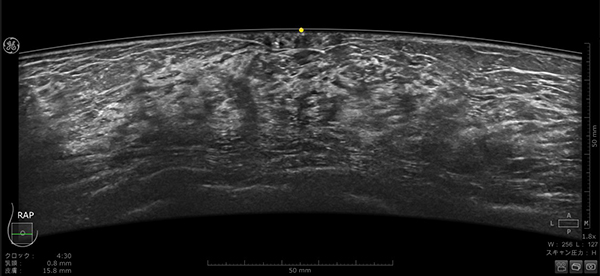

乳房にあてるプローブは,よりフィットするように設計され,周波数帯域も広がったことで空間分解能とコントラスト分解能が向上している。全ピクセルにフォーカスがあたる信号処理,乳頭直下が見えやすくなる画像処理は刷新され,より均一性の高い画像を提供する。

Invenia ABUS Premium で収集された乳房画像(乳頭直下「図黄色点」が描出されている)